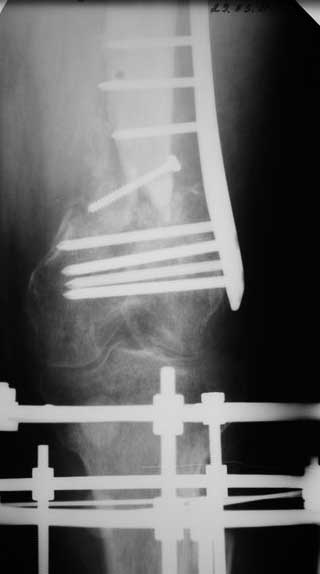

Уважаемые коллеги. Хотелось бы услышать Ваше мнение по следующему случаю. На лечении в отделении находится пациент 45 лет. С диагнозом: Замедленно консолидирующийся надмыщелковый перелом левой бедренной кости фиксированный пластиной от 06.12.10. Ложный сустав большеберцовой кости левой голени фиксированный АНФ от 06.12.10.

Стойкая контрактура левого коленного, голеностопного суставов. Укорочение левой нижней конечности на 5 см. Обширные кожные рубцы верхней трети левой голени. Хроническая венозная недостаточность левой нижней конечности.

Анамнез: травма 18.06.10 в результате ДТП, водитель. Диагноз: Сочетанная травма головы, конечностей. ЗЧМТ. Сотрясение головного мозга. Открытый многооскольчатый внутрисуставной перелом мыщелков и нижней трети левой бедренной кости со смещением отломков. Открытый перелом костей левой голени в верхней трети со смещением отломков. Обширные рвано – ушибленные раны левого бедра, верхней трети левой голени. Находился на лечении в нескольких стационарах, где проводились оперативные вмешательства.

7. 06.12.2010г. Открытая репозиция, остеосинтез чрезмыщеково – надмыщелкого перелома левой бедренной кости пластиной со свободной костной пластикой из гребня левой подвздошной кости (во время операции из за сомнений в жизнеспособности костного отломка перелома бедра произведено его удаление. За счет чего образовался дефект костной ткани и укорочение левого бедра на 5,0 см; Мыщелки бедра были в сгибание, 5 месяцев нога не опорная, при попытке их репонировать крошились , зафиксировали как стояли. Остеосинтез переломов костей левой голени в АНФ.

Местно: Ходит при помощи костылей с попыткой полной нагрузки на левую ногу. Левый коленный сустав в положении разгибания. Движения в коленном суставе качательные. Воспалительных явлений области послеоперационных рубцов, мест выхода спиц нет. Анализы крови без воспалительной реакции.

Бедро тут - аппаратом сильно не доработали, и дистальный отломок остался в рекурвации, и смещен на поперечник кзади. Так что мы бы малоинвазивно убрали пластину, аппаратом восстановили бы ось, и антеградно заштифтовали.